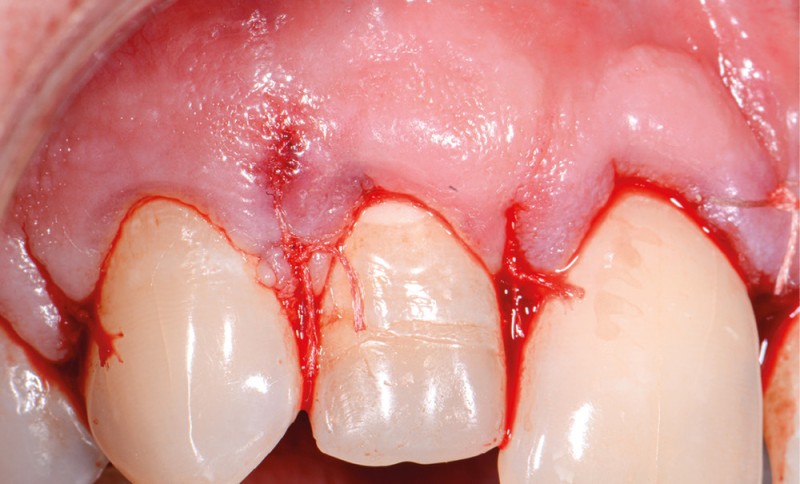

Ce type de perforation est également la plupart du temps iatrogénique et survient lors de la recherche ou de la mise en forme canalaire, lors de la préparation pour un logement de tenon radiculaire. Situées au niveau du plancher pulpaire des dents pluriradiculées, ou au niveau des entrées canalaires des dents monoradiculées ou pluriradiculées, il s’agit le plus souvent de perforations à quatre parois. Si la perforation survient en cours de traitement, elle doit être gérée immédiatement pour un meilleur pronostic (fig. 4). Néanmoins, il est important de prendre en compte l’épaisseur résiduelle du plancher. Si le plancher est trop fin, il ne sera pas possible d’envisager de traiter la perforation.

Les étapes 1 à 7 sont similaires à la situation 1.

Protocole pour la gestion d’une perforation du plancher avec la technique du tunnel (cela n’est réalisable que si le plancher est présent en épaisseur suffisante, ce qui n’est pas nécessairement le cas lors de perforations iatrogènes) :

8. irrigation régulière de sorte que la perforation soit en contact constant avec l’hypochlorite de sodium pour être désinfectée ;

9. en cas de perforation ancienne : retrait du tissu de granulation. La présence d’une lyse osseuse associée à une perforation indique généralement une lésion relativement ancienne où la communication s’est infectée. Le pronostic s’en trouve donc diminué [1, 2] ;